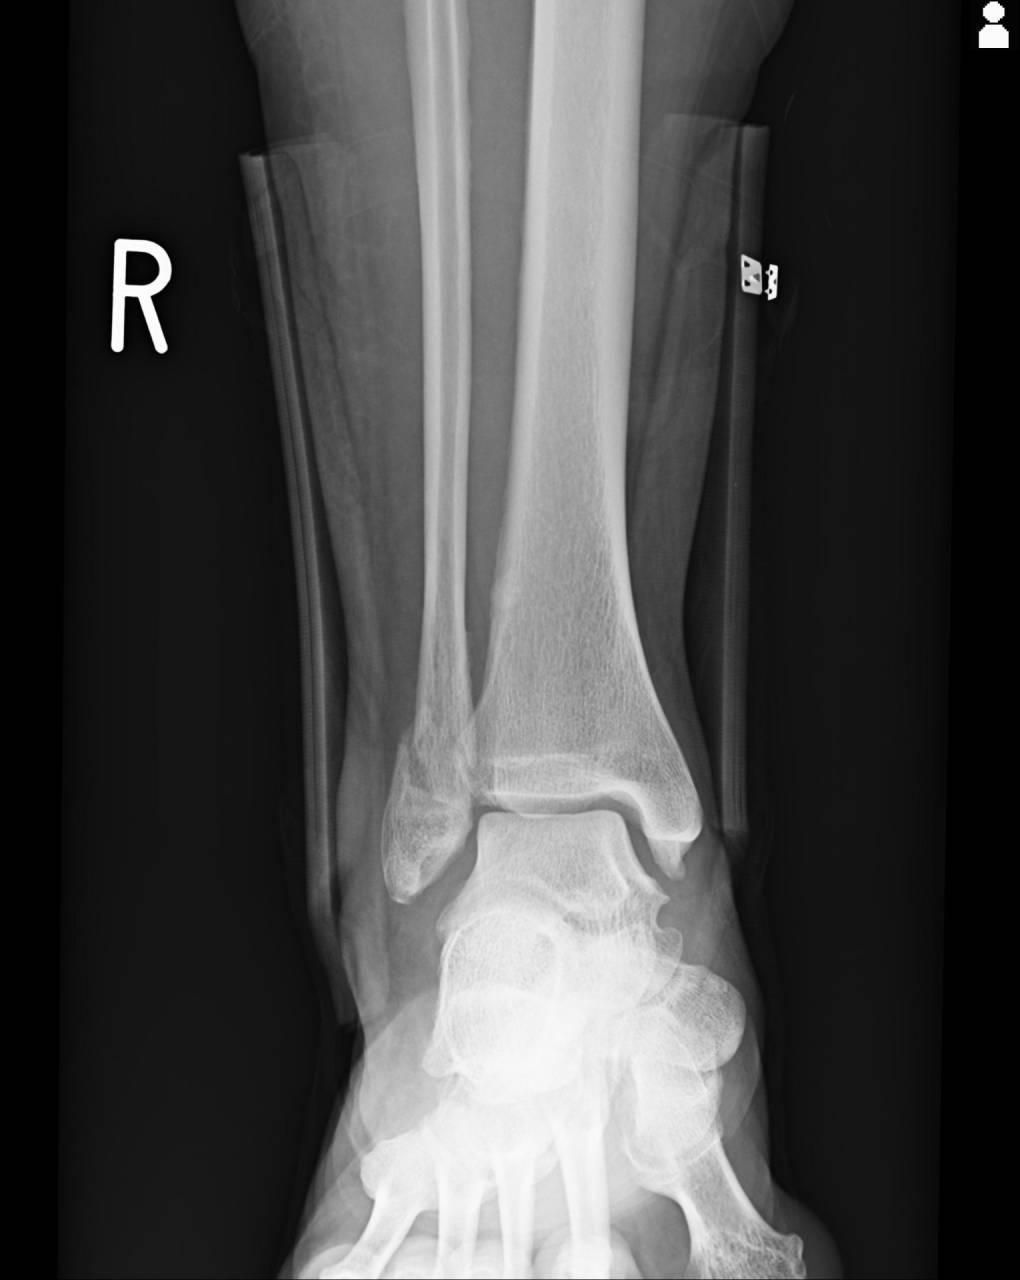

骨折の疑いが強いため、当整骨院が提携している病院にてレントゲン検査を依頼しました。

撮影した画像を確認すると外果部にエコーと徒手検査で怪しかった部位に骨折があり、若干の転位もありました。

腓骨の外果骨折として施術を進めていきます。